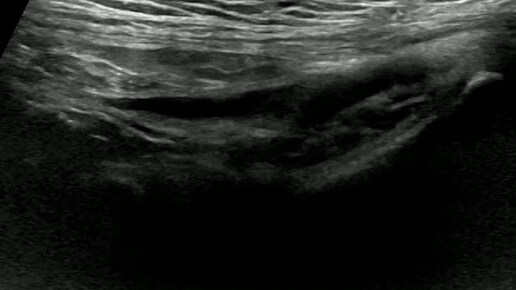

Видео к статье "Общие принципы ультразвуковой диагностики паховых грыж" https://dzen.ru/a/aC3gCR75zEo4_p-V